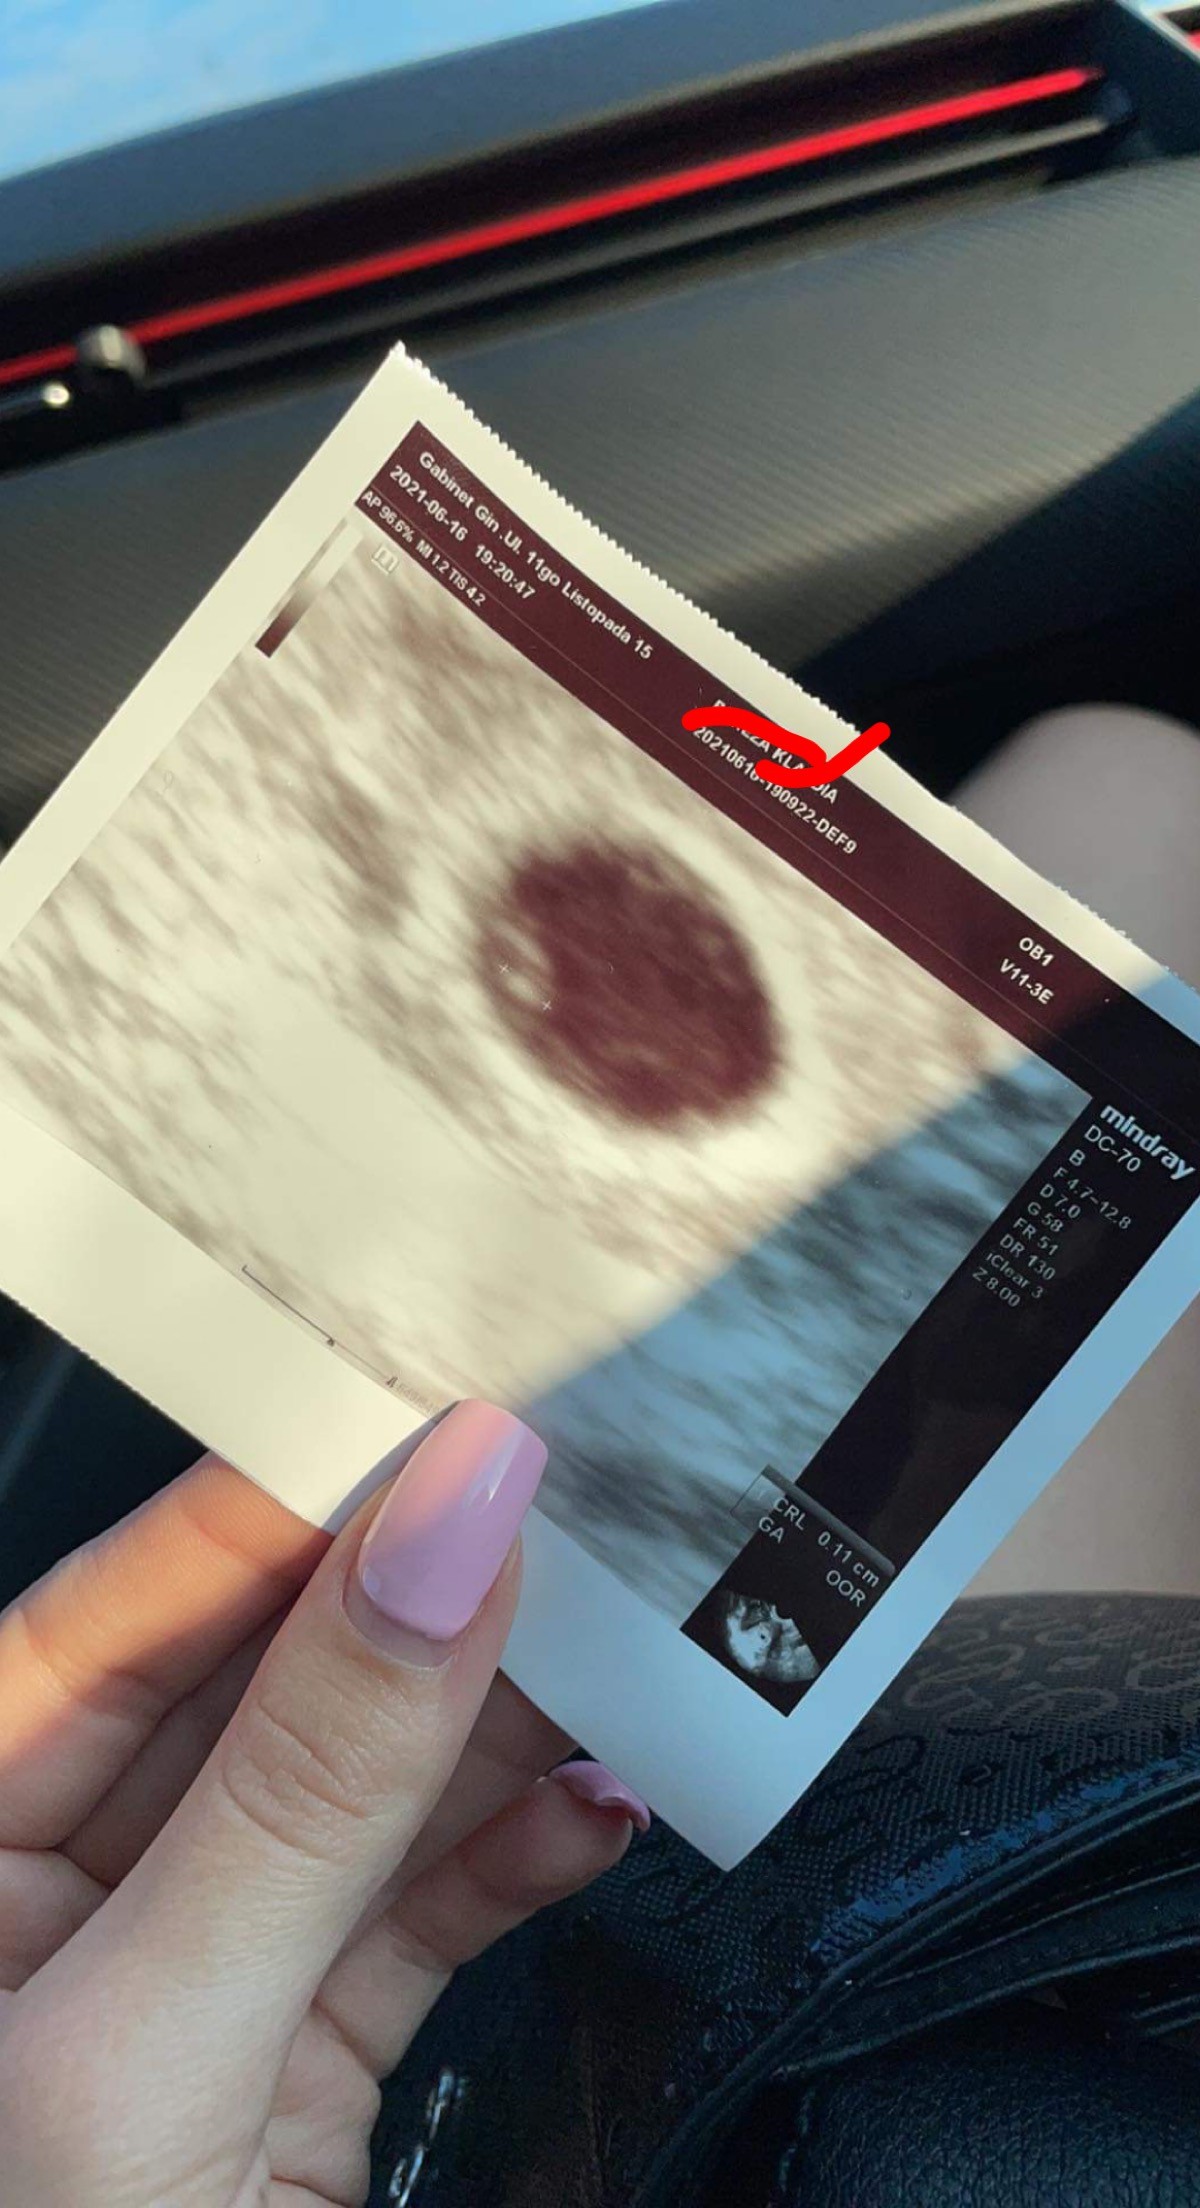

a zacznę od tego że wczoraj zaczęłam plamić dość obficie na taki beżowy kolor i od razu czarne myśli nerwy...ale jakoś się ogarnęłam i myślę sobie co ma być to będzie jakoś wytrzymie do dzisiejszej wizyty i na wizycie USG dopochwowe nic nie widać ja już serce w gardle ale gin mówi że może przez zrosty po CC słabiej widać (w tym gabinecie USG bardzo leciwe) i stwierdził sprawdzimy przez brzuch a tu kuźwa DWIE!!! Małe kuleczki

ale że słaby sprzęt to za tydzień mam przyjechać do innego gabinetu mojego gin i tam zobaczymy dokładniej co i jak. Na razie nie chce się cieszyć zabardzo bo z tymi początkami ciąży a zwłaszcza w bliźniaczych odpukac różnie bywa. A do tego luteina pod język 3razy dziennie i jakieś globulki na tą infekcje co mnie dopadła o której ostatnio pisałam.i na razie tyle u mnie za tydzień będę mieć lepszy obraz sytuacji.